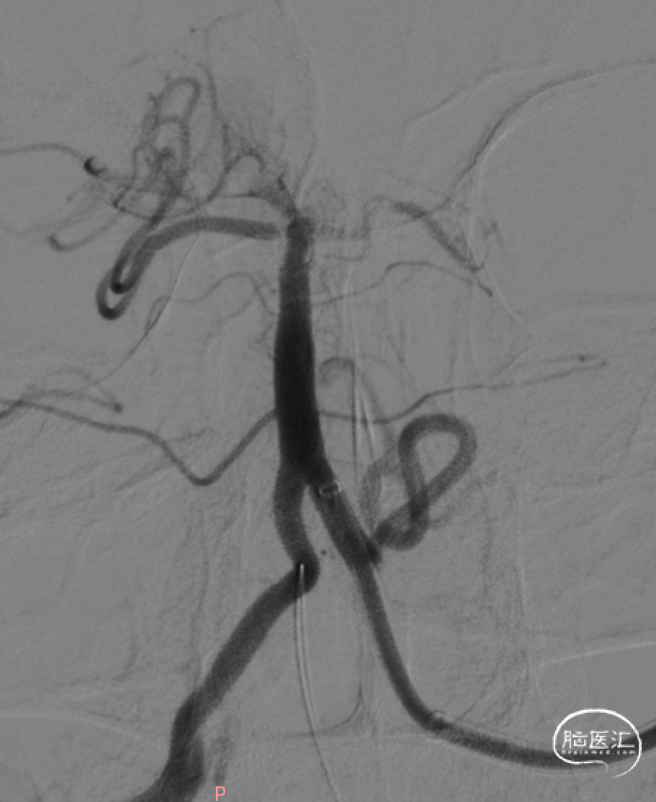

左侧椎动脉造影。

6F 125cm 通桥银蛇®颅内支持导管到位。

负压抽吸2次,基底动脉顶端部分再通,见栓子向双侧大脑后动脉逃逸。

微导丝携带微导管至右侧大脑后动脉P3段,抽拉结合取栓一次见右侧大脑后动脉再通。

微导丝携带微导管至左侧大脑后动脉P3段,抽拉结合取栓一次见左侧大脑后动脉再通。